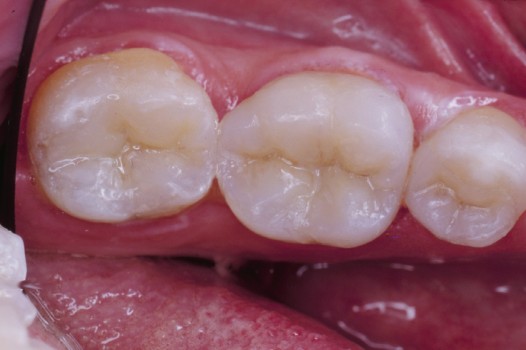

Traditional amalgam (mercury) fillings have been used for over a century, but concerns about health risks, tooth fractures, and long-term decay have led many dentists to adopt modern alternatives. Today, metal-free restorations offer healthier, stronger, and more natural-looking results.

Using advanced resins, ceramics, and state-of-the-art bonding techniques, Dr. Klim can restore teeth with precision, preserving healthy tooth structure while preventing fractures, bacterial invasion, and future toothaches.